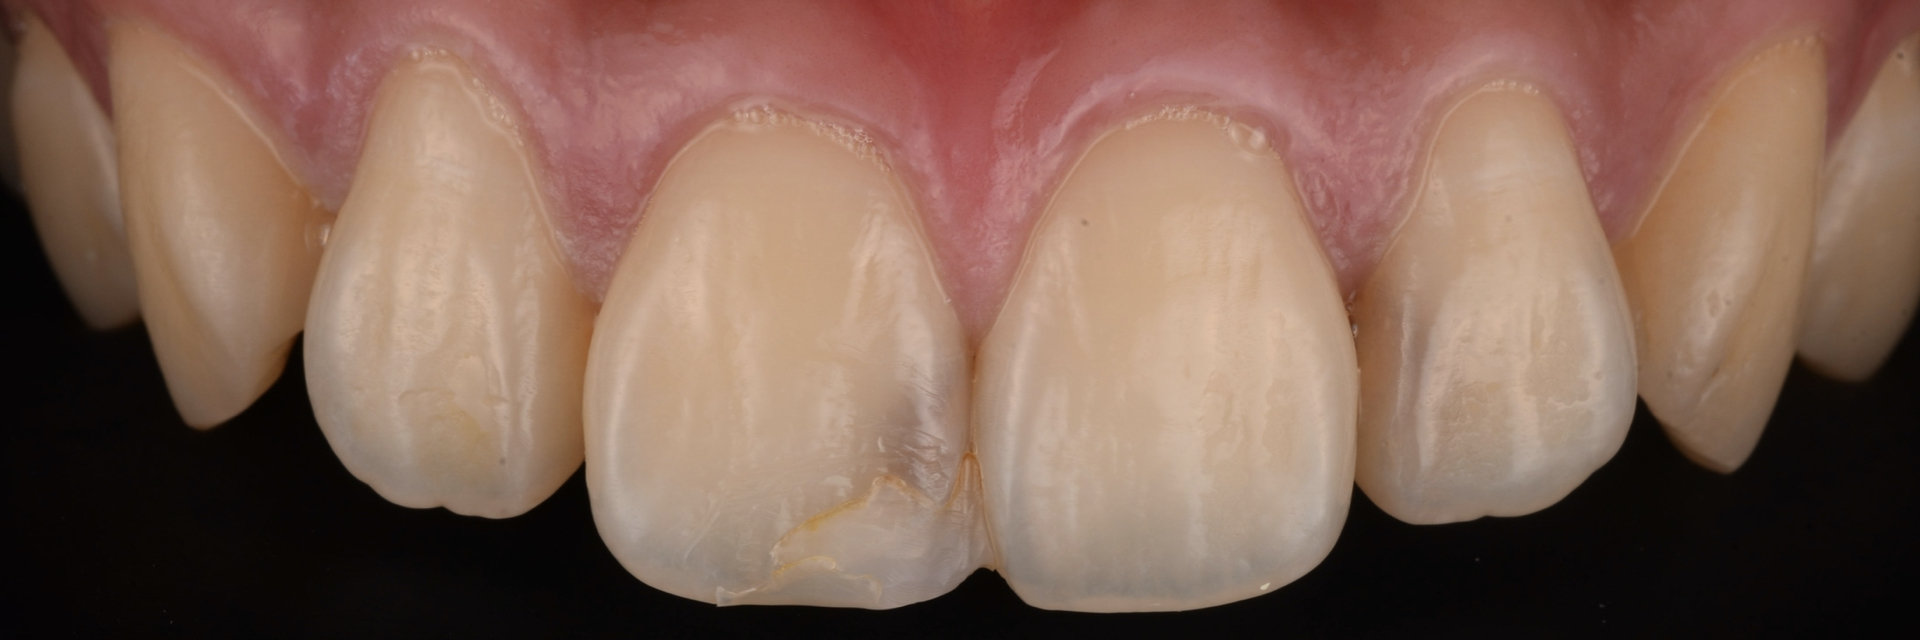

治療前